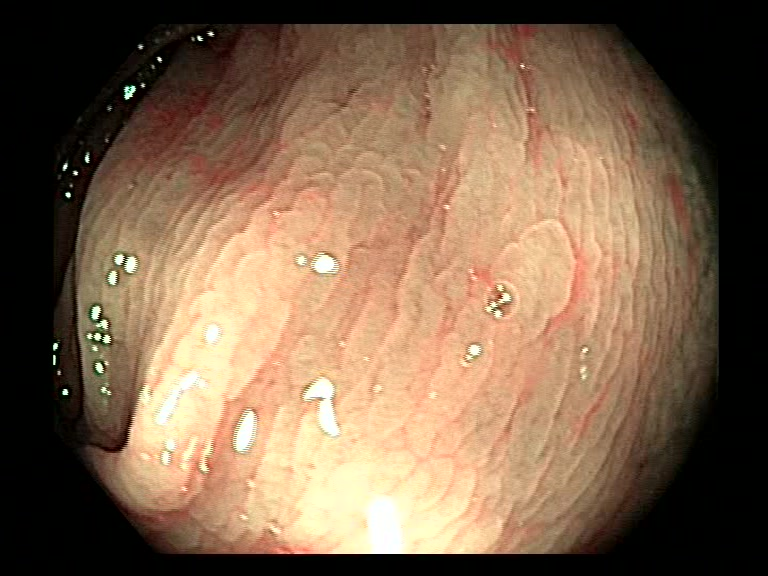

| Lesion | White Light Frame | NBI Frame | White Light Video | NBI Video | Camera Calibration |

| hyperplasic_01 |  |

|

WL.mp4 | NBI.mp4 | cam.xml |